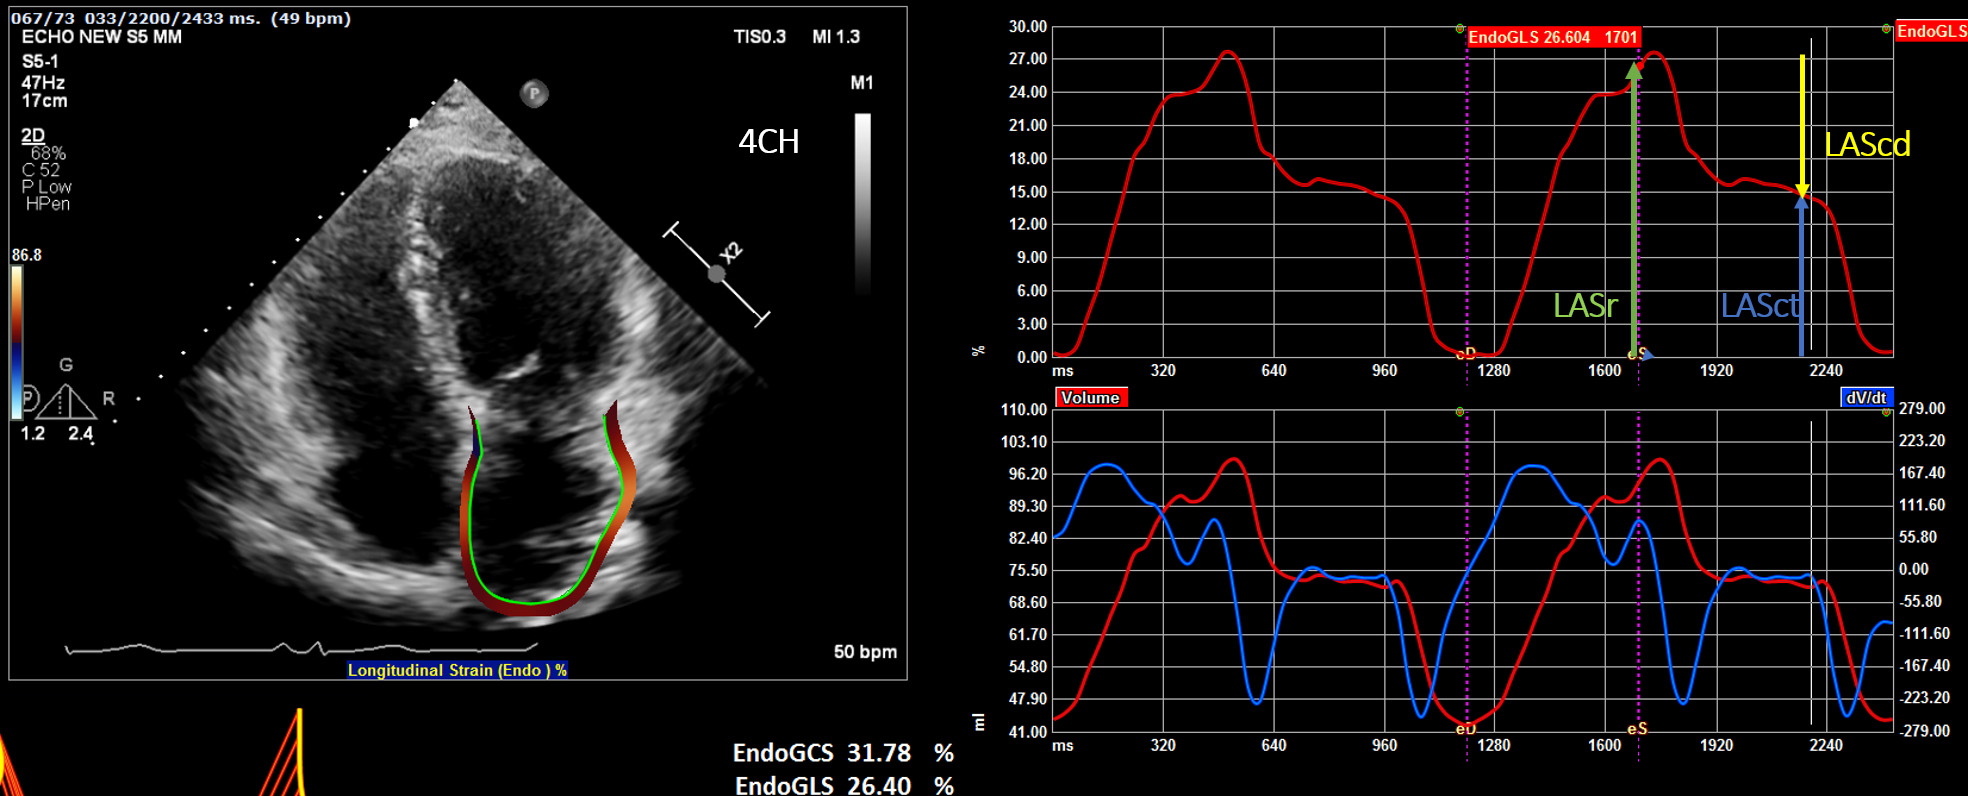

(a) Reservoir phase—LASr (left atrial reservoir strain): atrial diastole (occurs during ventricular systole)—begins at the end of ventricular diastole (mitral valve closure) and continues until mitral valve opening. Represents the time of LV isovolumic contraction, ejection and isovolumic relaxation (Fig. 1).

Fig. 1.Display of the left atrial deformation over a cardiac cycle, starting at the QRS as zero reference point. The peak positive longitudinal strain (LAS) corresponds to atrial reservoir function (LASr — reservoir strain), strain during early diastole reflects atrial conduit function (LAScd — conduit strain) and strain during late diastole corresponds to atrial contractile function (LASct — LA contraction strain).

(b) Conduit phase—LAScd (left atrial conduit strain): passive atrial systolic phase during ventricle diastole. Starts with mitral valve opening through diastasis until the onset of LA contraction in patients with sinus rhythm. In patients with AF, it continues until the end of ventricular diastole (mitral valve closure).

(c) Contraction phase—LASct (left atrial contraction strain): starts with the onset of LA contraction until the end of ventricular diastole (mitral valve closure) in patients with sinus rhythm.

(1) Zero strain reference set at left ventricular end-diastole-recommended (Fig. 1).